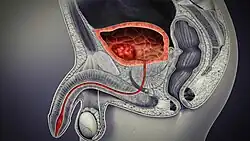

Cross-section of the male genitourinary system showing a cancer within the bladder. When a cancer occurs it is most likely to be a transitional cell carcinoma.

Cancer of the bladder is known as bladder cancer. It is usually due to cancer of the urothelium, the cells that line the surface of the bladder. Bladder cancer is more common after the age of 40, and more common in men than women;[33] other risk factors include smoking and exposure to dyes such as aromatic amines and aldehydes.[33] When cancer is present, the most common symptom in an affected person is blood in the urine; a physical medical examination may be otherwise normal, except in late disease.[33] Bladder cancer is most often due to cancer of the cells lining the ureter, called transitional cell carcinoma, although it can more rarely occur as a squamous cell carcinoma if the type of cells lining the urethra have changed due to chronic inflammation, such as due to stones or schistosomiasis.[33]